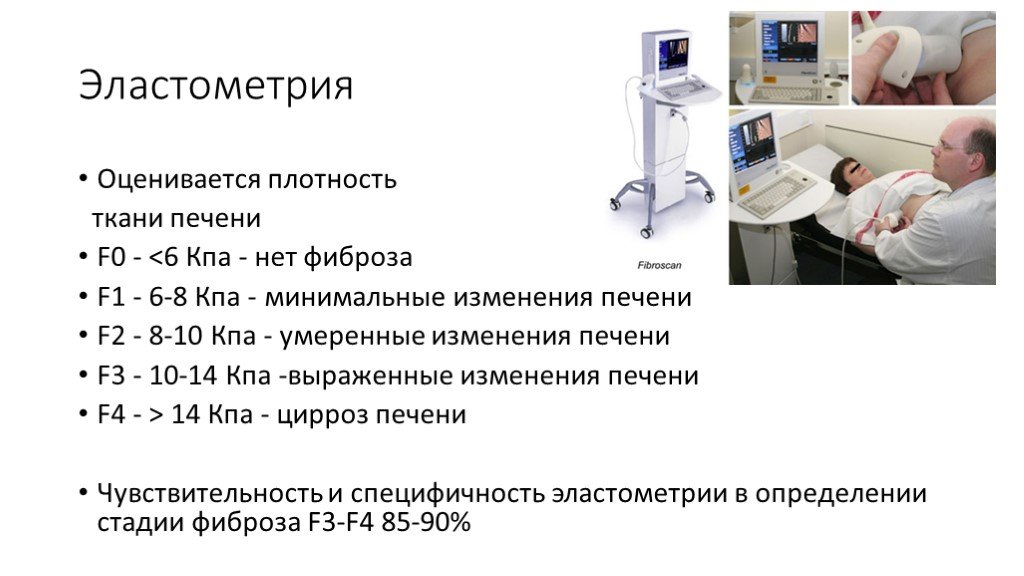

Эластометрия брюшной полости – это современный метод диагностики, который позволяет оценить состояние тканей органов в брюшной полости с помощью ультразвуковых волн. Это исследование помогает выявить различные заболевания на ранних стадиях, таких как цирроз печени, фиброз, воспалительные процессы и другие патологии, что способствует своевременному назначению эффективного лечения.

Эластометрия печени. Что? Где? Когда?

Эластометрия печени. Покажет то, что не видно на УЗИ и в анализах.

Эластометрия - как метод мультипараметрического УЗИ. Большое интервью с доктором Пеняевой Э.И.